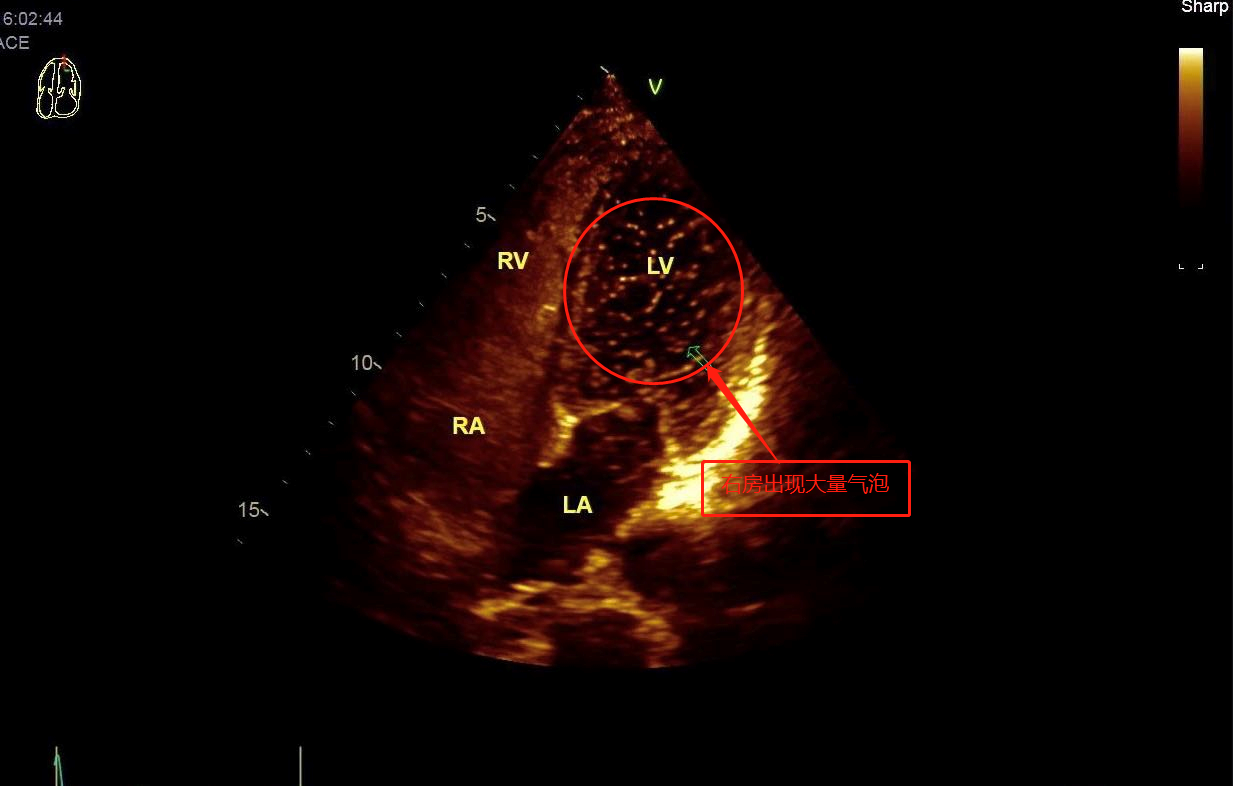

家住华容县32岁的叶女士是一位长期顽固性偏头痛的患者,服药后头疼症状无明显减轻,于是到华容县人民医院就诊。3月18日,医院超声科吴小勇主任为她进行了科室开展的新技术——右心声学造影,超声提示叶女士的心脏卵圆孔处多了个“心眼”,造成明显的右向左分流现象,至此,叶女士头痛的原因终于得以找到了最终,叶女士在行“房缺封堵术”后,多年的头痛症状明显缓解。

对此,超声科医师建议,对于常规检查无法找到原因的缺血性脑卒中,偏头痛,脑梗患者推荐进行右心声学造影检查。此项检查对病情诊断有着较高的参考价值。